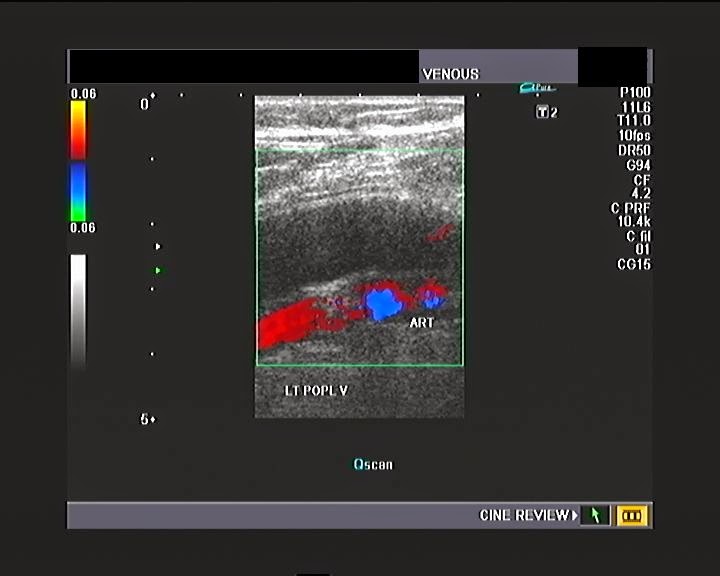

From ultrasound-images.blogspot.com

Ultrasound imaging A patient of calf and leg pain venous Doppler study Doppler X-Ray a doppler ultrasound is a type of ultrasound imaging test that uses sound waves to show how well your blood flows through your. a doppler ultrasound can detect differences in pitch as blood cells move through your blood vessels. Then, it converts this sound data into a picture or graph. a doppler ultrasound can help check whether. Doppler X-Ray.